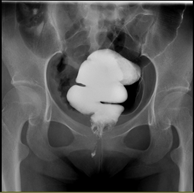

结合肛管MR提示有一瘘道可疑通往直肠下段,进一步行结肠造影显示“直肠末端见条线状影向前下方延伸,长度约18mm,末端稍膨大,范围约10mm×7mm”,提示直肠瘘口存在(图2)。”

图2  结肠造影